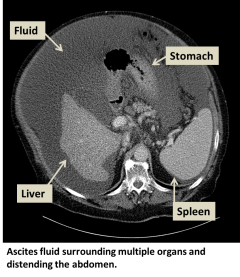

Ascites is the accumulation of fluid in the peritoneal cavity, the potential space around the organs within the abdomen. Ascites is caused by fluid leaking out from blood vessels as a result of various disease processes.

Ascites can be detected with a physical exam or ultrasound. Your physician may look for "shifting dullness" to check if abdominal sounds change as the abdominal fluid moves.